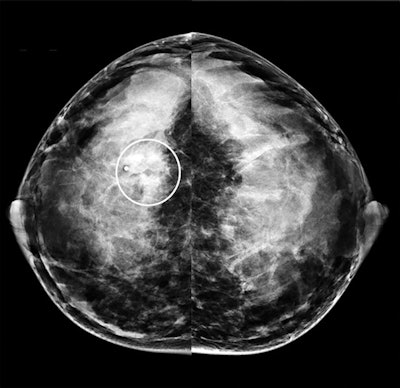

Craniocaudal mammogram from the same 40-year-old patient with invasive ductal carcinoma. The patient's mammogram images show a subtle, obscured mass at the site of the palpable abnormality (region of interest) with some associated amorphous calcifications.

Mediolateral oblique mammogram from the same 40-year-old patient with invasive ductal carcinoma. Both mammograms depict heterogeneously dense breast tissue.The authors attributed mammography's lower specificity due to the modality's struggle depicting cancers in dense breast tissues during pregnancy and lactation. Notably, 98% of the patients in the study had dense breast tissue, including 72% of whom had extremely dense breast tissue.